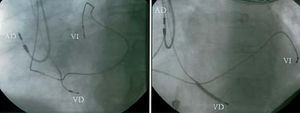

Se definió zona anterior a la comprendida entre las 10 y la 1 en la posición radiológica oblicua anterior izquierda a 45° y zona lateral a la comprendida entre las 2 y las 5 en la misma proyección (fig. 1).

Fig. 1. Imágenes radiológicas en proyección oblicua anterior izquierda a 45°. El electrodo ventricular izquierdo se encuentra localizado en zona anterior (imagen izquierda) y en posición lateral (imagen derecha). AD: electrodo auricular derecho; VD: electrodo ventricular derecho; VI: electrodo ventricular izquierdo.